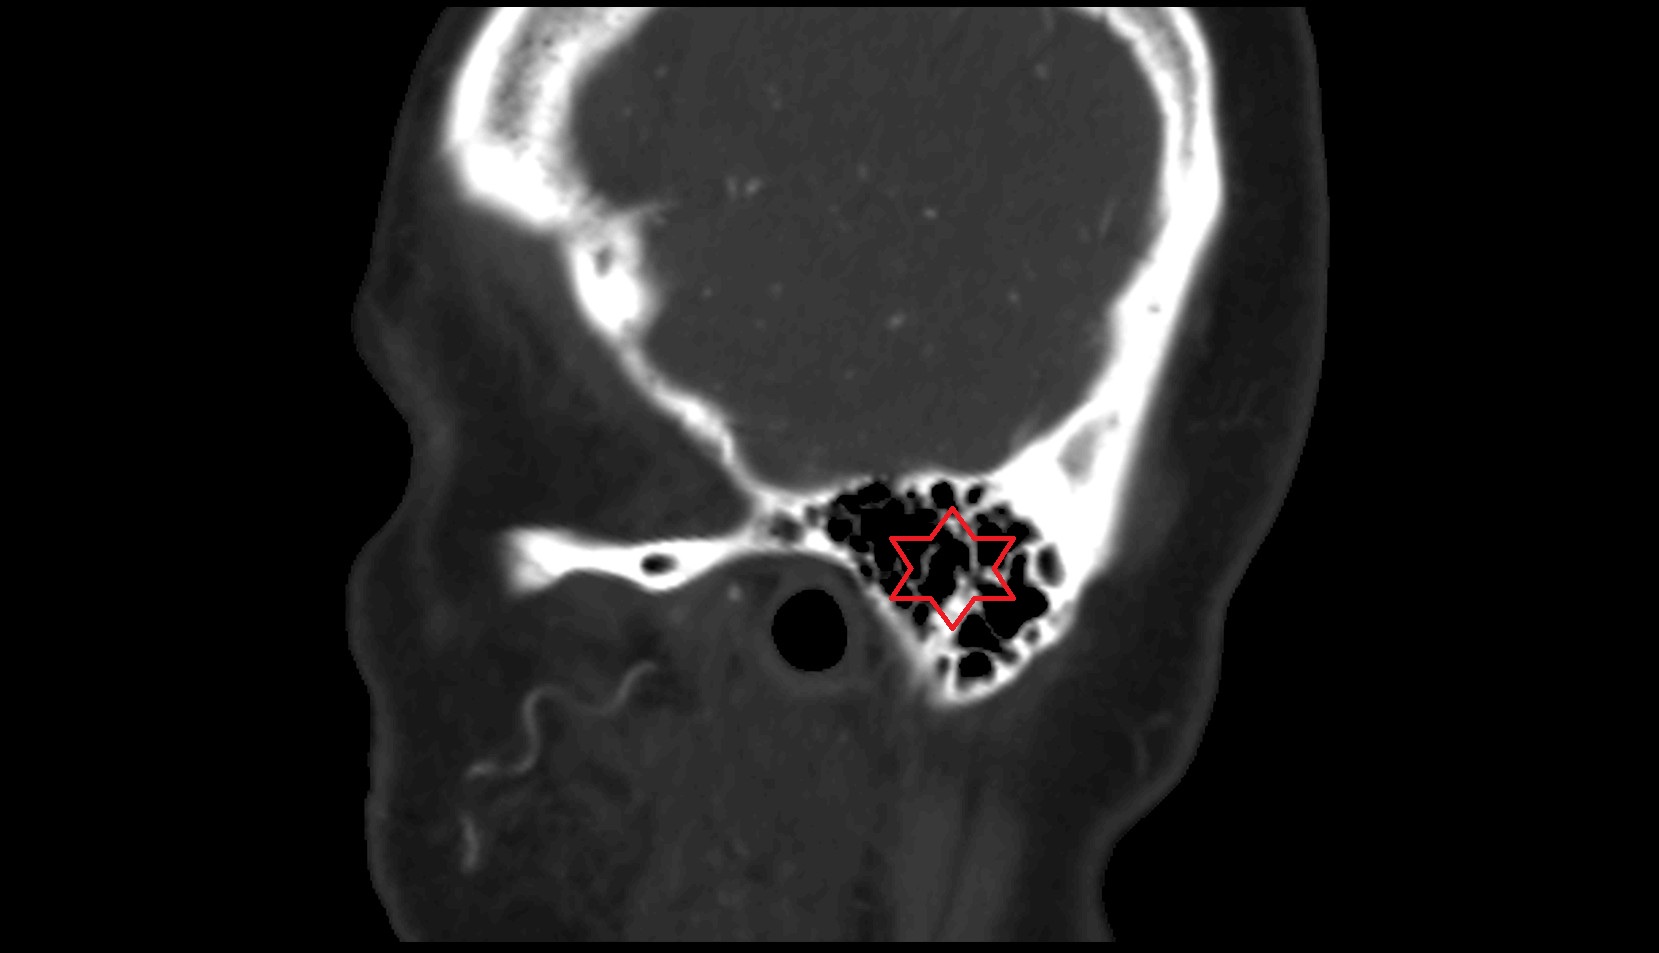

- Jugular foramen

- jugular foramen pars nervosa

- Jugular foramen pars vascularis